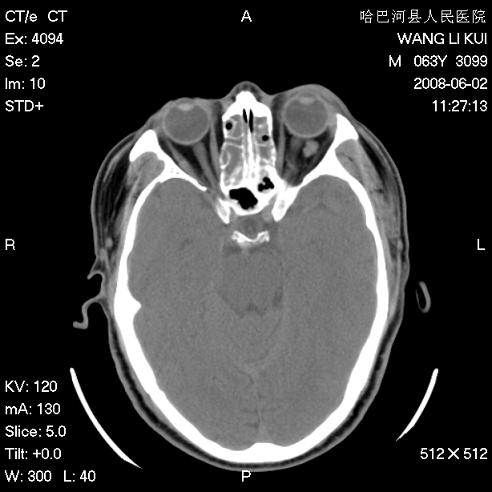

标题: CT13803:反复性鼻塞、流涕一年余 [打印本页]

标题: CT13803:反复性鼻塞、流涕一年余

副鼻窦炎,右上额窦积脓。左眼肌锥内见致密影,视神經受压

全组副鼻窦炎 肌锥内高密度灶。建议进一步检察检查

1、全组副鼻窦炎。

2、左眼眶肌锥内病变,小血管瘤?建议增强。

1)全副鼻窦炎(左侧上颌窦黏膜下囊肿或息肉)。2)左眼眶肌锥内不规则小结节状软组织密度影;考虑为小血管瘤可能。建议行ct增强扫描检查。

全组副鼻窦炎,左侧肌锥内不规则形软组织肿块影,与眼外肌密度相当,左侧视神经受压,肿块与视神经及眼外肌分界清晰,眼外肌无增粗,眶壁无破坏,球后脂肪间隙不模糊,考虑良性改变,小血管瘤或神经源性肿瘤可能,建议增强扫描。

谢谢,增强扫描做了,眶内病灶与海绵窦同步明显强化,血管瘤